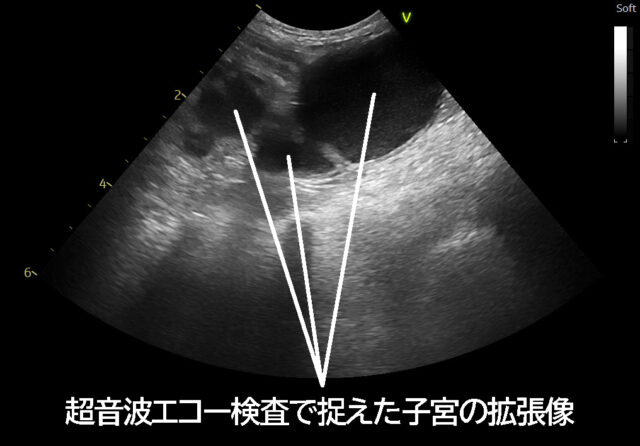

・超音波エコー検査:子宮内に膿が溜まっていないか確認

膿がたまって拡張した子宮